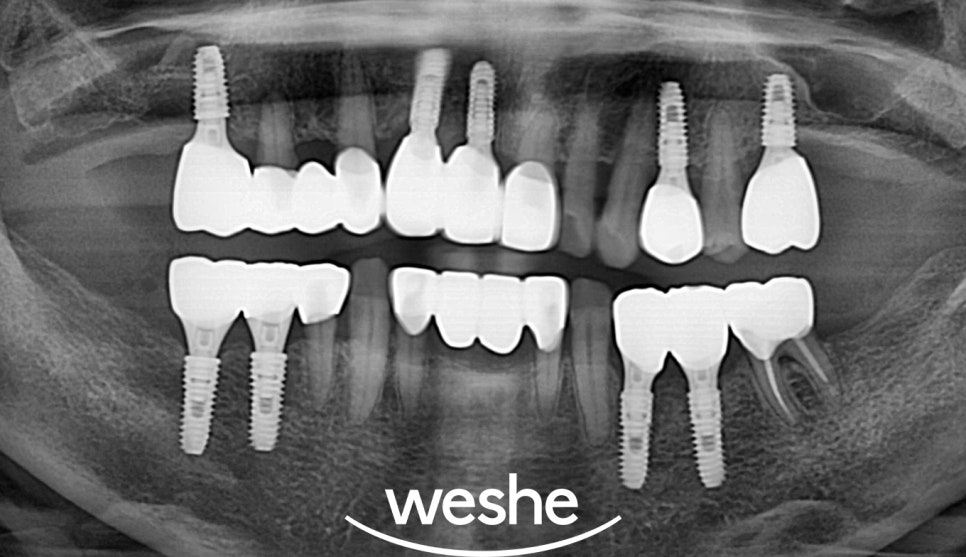

치주질환과 치간이개를

동반한 경우의 임플란트 치료는

단계적으로 진행됩니다.

먼저 급성 염증을 조절하기 위해

치주치료를 시행합니다.

스케일링을 통해 치석을 제거하고,

필요한 경우 치근 활택술을 통해

뿌리 표면의 치석과 염증을 제거합니다.

보존이 불가능한 치아의

발치는 신중하게 계획해야 됩니다.

발치 과정에서

주변 조직의 손상을 최소화하고,

향후 임플란트 식립을 위해

경우에 따라서,

발치와 동시에 골이식을 시행하여

임플란트 식립을 위한

충분한 골량을 확보합니다.

임플란트 식립 전에는

잇몸 염증이 조절되어야 됩니다.

픽스처가 턱뼈와 단단히

결합되는 골유착 과정에는

일반적으로 3-6개월의 시간이 필요합니다.

골유착이 완료된 후에는

최종 보철물을 제작하여

자연스러운 치아 형태와

기능을 회복합니다.